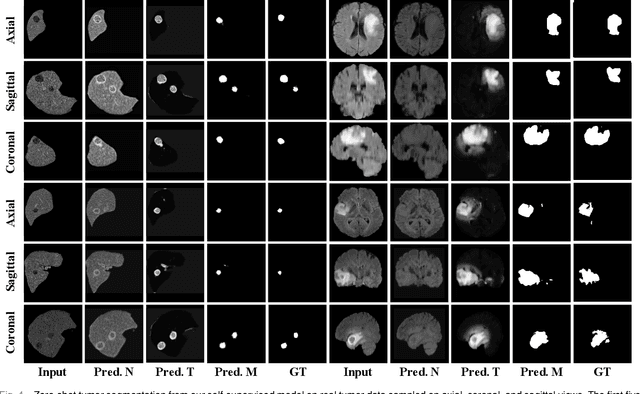

Abstract:In this paper, we propose a self-supervised approach for tumor segmentation. Specifically, we advocate a zero-shot setting, where models from self-supervised learning should be directly applicable for the downstream task, without using any manual annotations whatsoever. We make the following contributions. First, with careful examination on existing self-supervised learning approaches, we reveal the surprising result that, given suitable data augmentation, models trained from scratch in fact achieve comparable performance to those pre-trained with self-supervised learning. Second, inspired by the fact that tumors tend to be characterized independently to the contexts, we propose a scalable pipeline for generating synthetic tumor data, and train a self-supervised model that minimises the generalisation gap with the downstream task. Third, we conduct extensive ablation studies on different downstream datasets, BraTS2018 for brain tumor segmentation and LiTS2017 for liver tumor segmentation. While evaluating the model transferability for tumor segmentation under a low-annotation regime, including an extreme case of zero-shot segmentation, the proposed approach demonstrates state-of-the-art performance, substantially outperforming all existing self-supervised approaches, and opening up the usage of self-supervised learning in practical scenarios.